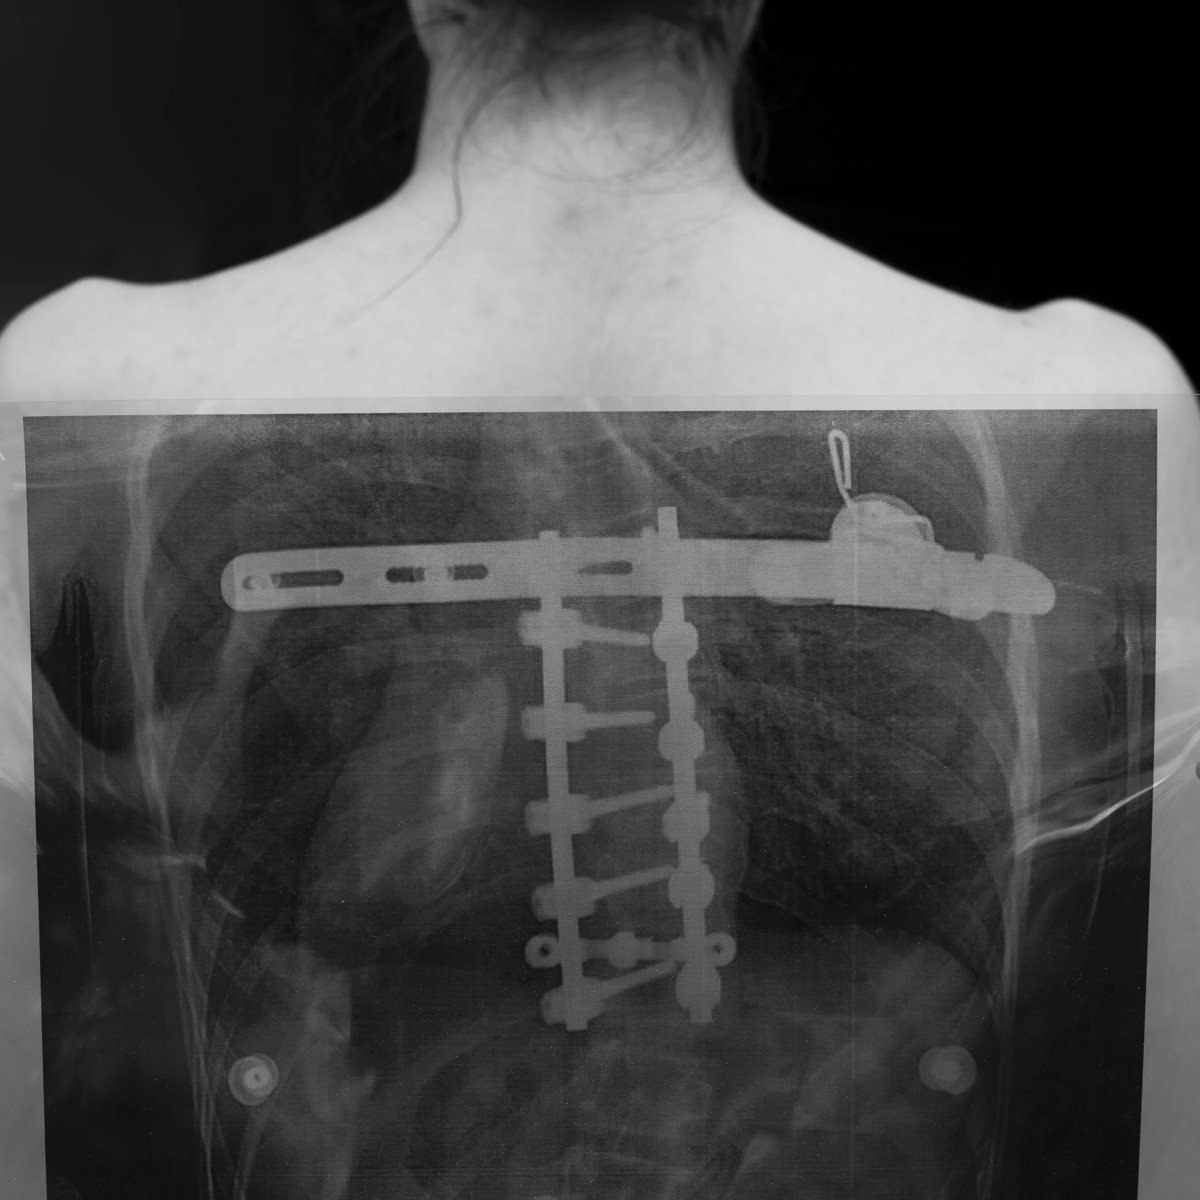

Každý člověk má jizvy. Ne všichni máme odvahu si je přiznat. Možná je máme krátce a cítíme, jak pálí. Možná v nás existovaly odjakživa. Někdy jde o genetické vady, poškození získané v dětství nebo mnohem později. Ne každý se umí postavit čelem k tomu, co je pro něj bolestivé, a proto jizvy nejčastěji zůstávají skryté pod oblečením, make-upem a úsměvy. I když nejsou vidět, hlavní hrdina cítí, že tam jsou, a zdá se mu, že je vidí i ostatní. Jizva nemá jen doslovný význam, ale týká se především citové a psychické sféry. Zásahy, které jsou překryty fotografiemi, zdůrazňují bolest, která jizvy provází, ztrátu sebedůvěry, někdy dotek smrti a vzpomínku na to, jak se tělo a psychika změnily. Jaký význam má jizva? Kolik jizva váží? Snaha zkrotit, zpracovat a vypořádat se s traumatem ne vždy funguje. Jizvu nelze vyhnat z paměti ani z těla. Na většině fotografií jsou vidět jen fragmenty, postavy neukazují svou tvář. Záměrem bylo vytvořit univerzální projekt. Když se díváme na fotografii, nevidíme nutně cizího člověka, ale sami sebe, někoho blízkého, a přemýšlíme, jak vnímáme „deformace“. Projekt vznikal v letech 2022 až 2024 v Polsku, Česku, Francii, Belgii.